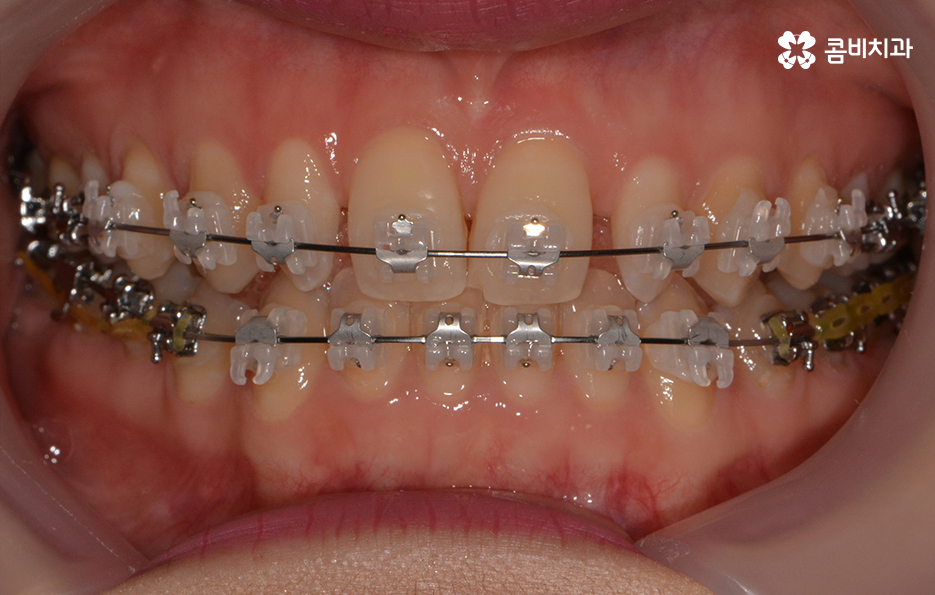

전체적인 치열 상태가 비교적 가지런한 편이었기 때문에

약 1년 정도 클리피씨교정을 통해서 치열과 교합 개선이 진행 되었습니다.

치아교정은 치열을 가지런하게 만드는 과정 만이 아니라

치아의 각도 차이만으로도 결과에 대한 만족도가 크게 달라질 수 있으며

얼굴과 자연스럽게 어울려야 하기 때문에 전체적인 조화가 중요합니다.